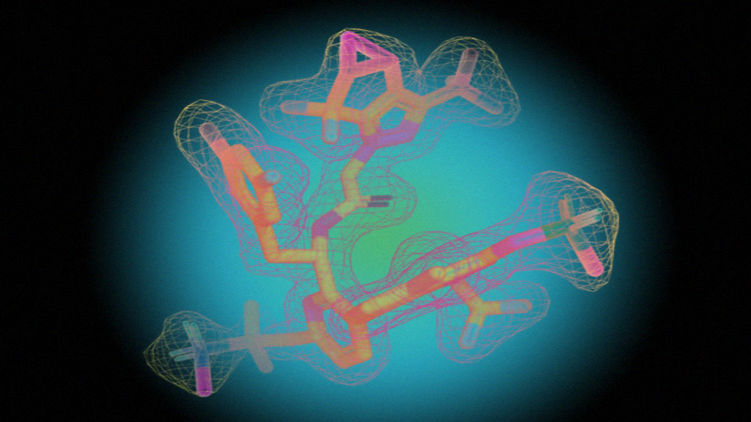

Сотрудники американской биофармацевтической компании Gilead Sciences разработали и испытали антиретровирусный препарат нового класса. Молекула лекарства нарушает работу белка капсида (внешней оболочки) ВИЧ и препятствует размножению вируса.